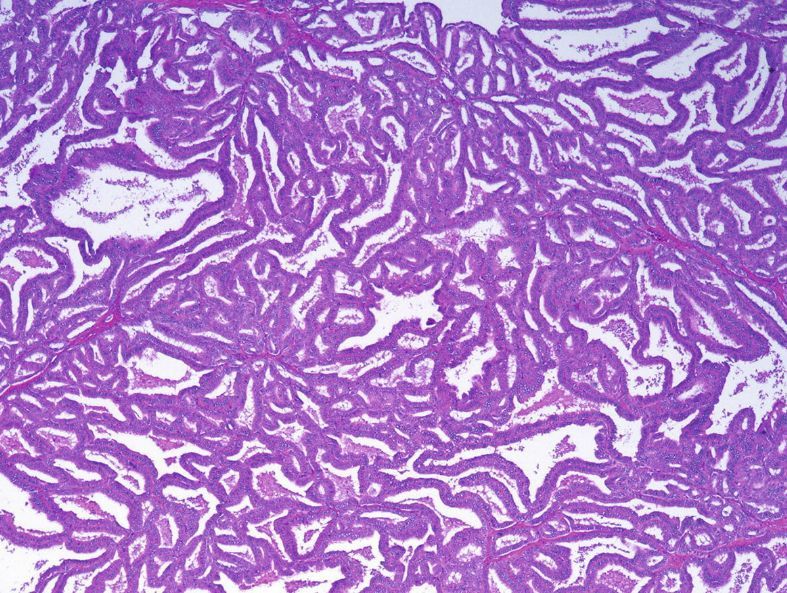

Papillary renal cell carcinoma

Cellular tumor of pink-to-blue cells that may be arranged in papillary formation, solid sheets, or trabecular cords.

The classic histologic pattern is that of a fibrovascular core packed with foamy macrophages and lined by cuboidal cells with round nuclei. This image is pathognomonic. Psamomma bodies, hemosiderin-laden macrophages, and focal clear cells may also be seen.

Tumors are divided into Type 1 (low nuclear grade) and Type 2 (high nuclear grade).